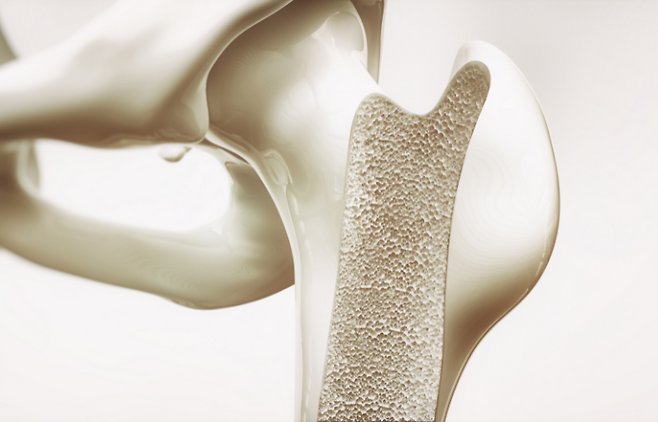

관절염은 단순히 나이가 들어서 생기는 관절의 마모가 아니다. 실제로는 몸속 염증이 오래 쌓이면서 연골과 주변 조직이 손상되고, 통증과 부종이 반복되는 만성 염증 질환이다. 약물치료가 기본이지만, 식단을 잘 관리하면 염증 신호를 크게 줄이고 관절의 회복 속도를 높일 수 있다. 그중 과학적으로 가장 많은 연구가 된 대표 식품이 바로 연어다.